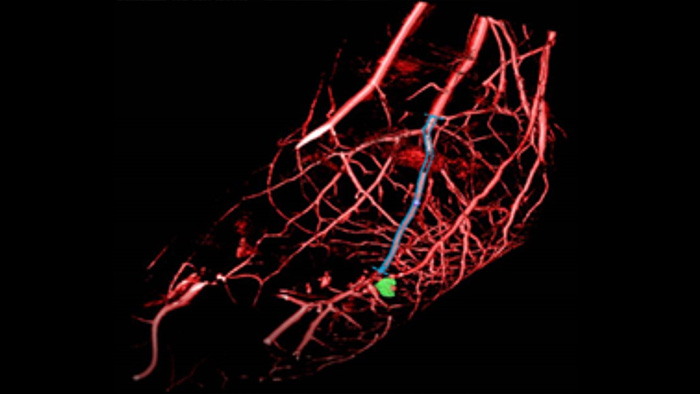

Die SmartCT Roadmap erleichtert komplexe Verfahren durch segmentierbare Live-3D-Bildführung, um das Zielgefäß sowie die Läsionen hervorzuheben und so die Navigation durch komplexe Gefäßstrukturen zu unterstützen. Sämtliche Funktionen werden über den Touchscreen am Tisch gesteuert.